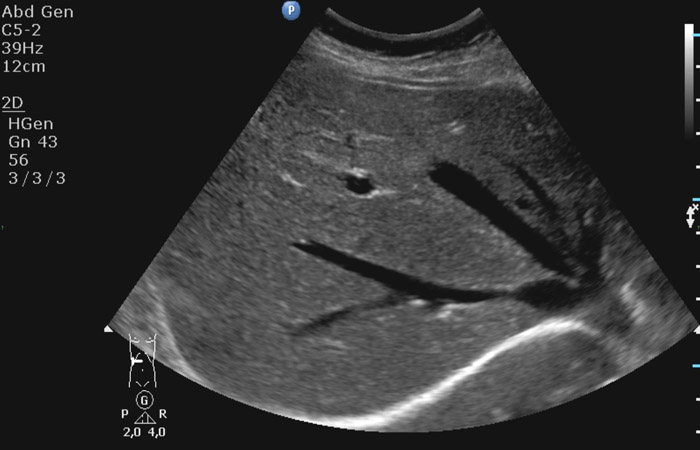

Η μελέτη του ήπατος δίνει στοιχεία για το μέγεθος, το σχήμα του οργάνου καθώς και την παρουσία ή όχι διάχυτων (λιπώδης διήθηση) ή εστιακών (κύστεις, αιμαγγειώματα, καλοήθεις ή κακοήθεις όγκοι) αλλοιώσεων στο παρέγχυμά του.

Ο έλεγχος της χοληδόχου κύστης παρέχει πληροφορίες για την παρουσία περιεχομένου ενδοαυλικά (ίζημα-λίθοι), καθώς και για το τοίχωμά της ( πάχος τοιχώματος-παρουσία φλεγμονής, ανάδειξη πολυπόδων ή άλλης εξεργασίας).

Η απεικόνιση του παγκρέατος παρέχει στοιχεία όσον αφορά την υφή του οργάνου και την παρουσία εστιακών βλαβών (ψευδοκύστεις, συμπαγείς εξεργασίες).